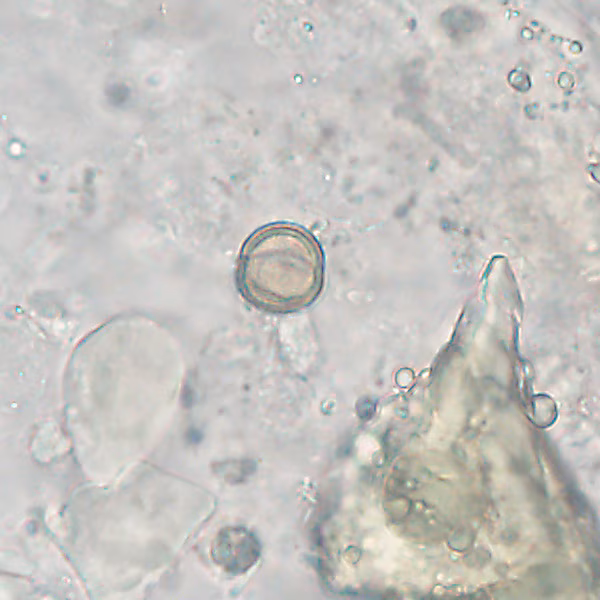

A 42-year-old State Park employee sought medical care due to fatigue, insomnia, intermittent bloating, and mild anemia. He provided additional information that he often ate various plants (nuts, seeds, and berries) he encountered while on patrol. A stool specimen was collected and processed for ova and parasite (O & P) examination. Figures A and B show what was detected in moderate numbers on a wet mount. Size of the objects was approximately 20 micrometers in diameter. What is your diagnosis? Based on what criteria?

Figure A